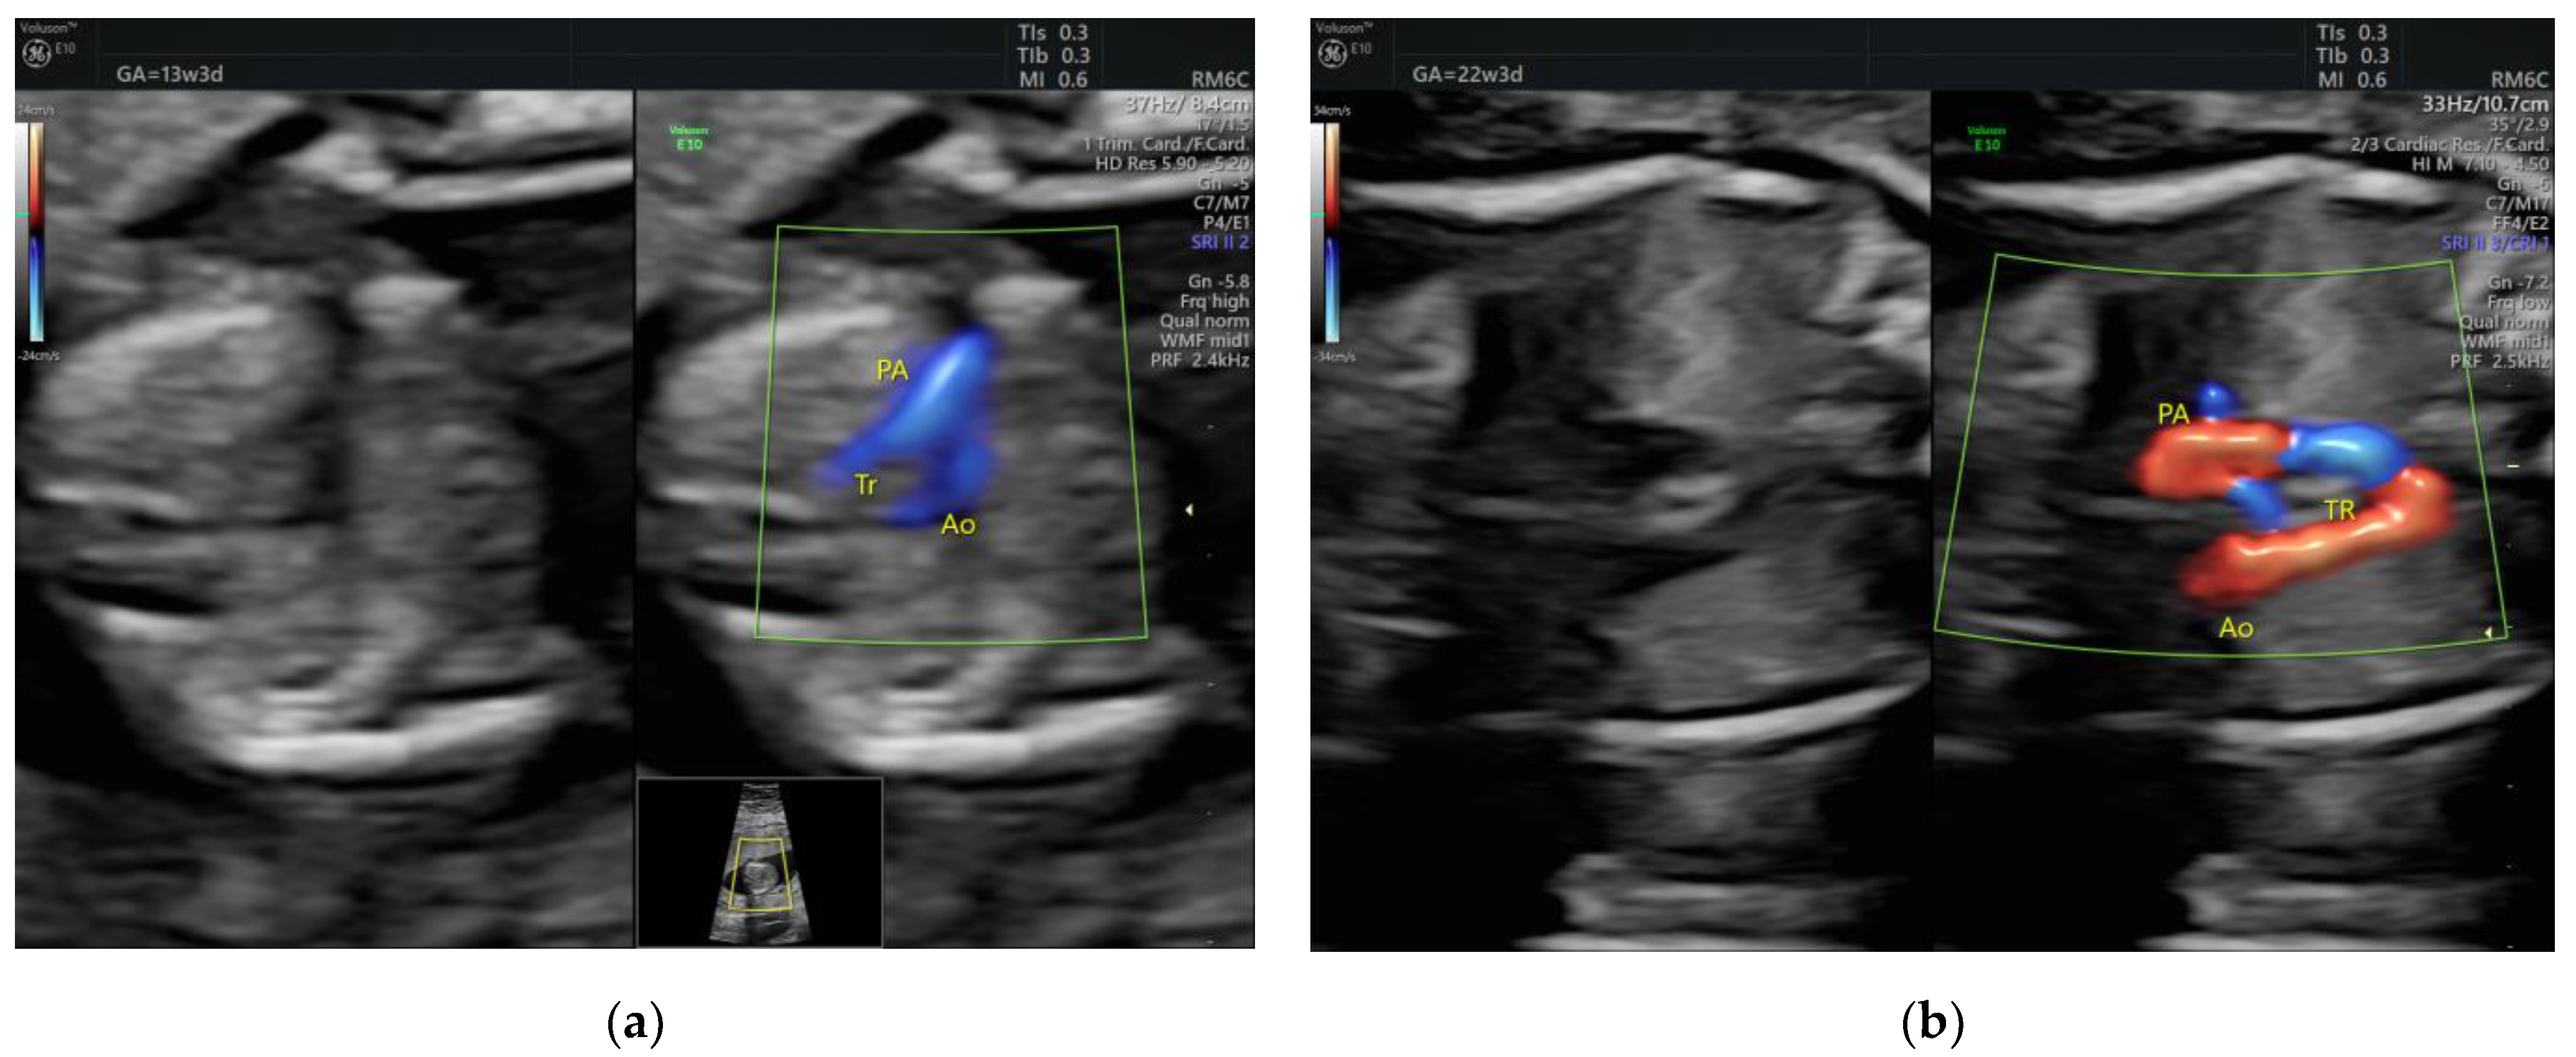

| Fallot | 1 | - | - | 3VT | + | 0 | 1 | 0 | 1/1 |

| RAA | 1 | - | perimembranous VSD | 3VT | + | 1 | 0 | 0 | 1/1 |